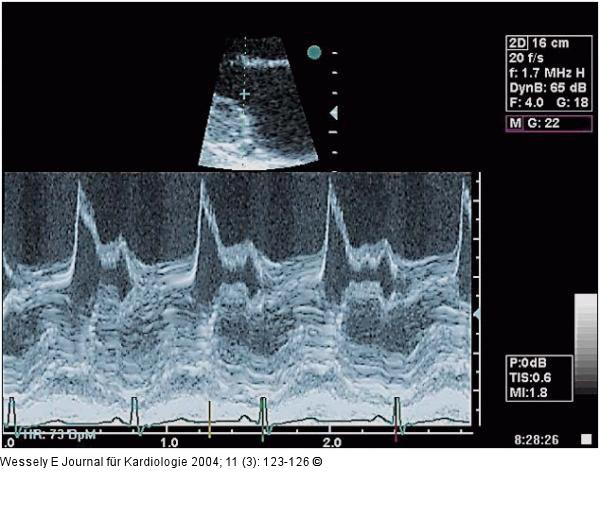

Abbildung 2: Aortenklappeninsuffizienz - Endokarditis Sogenannter "diastolischer shudder" des vorderen Mitralsegels in der M-Mode-Registrierung (parasternal lange Achse) |

Abbildung 2: Aortenklappeninsuffizienz - Endokarditis

Sogenannter "diastolischer shudder" des vorderen Mitralsegels in der M-Mode-Registrierung (parasternal lange Achse) |